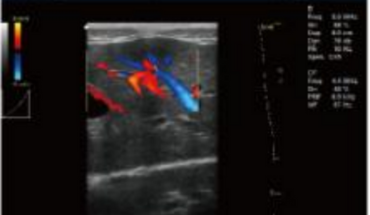

- B+CF (Images doubles)

- B+CF/DPDI+PW (Triplex)